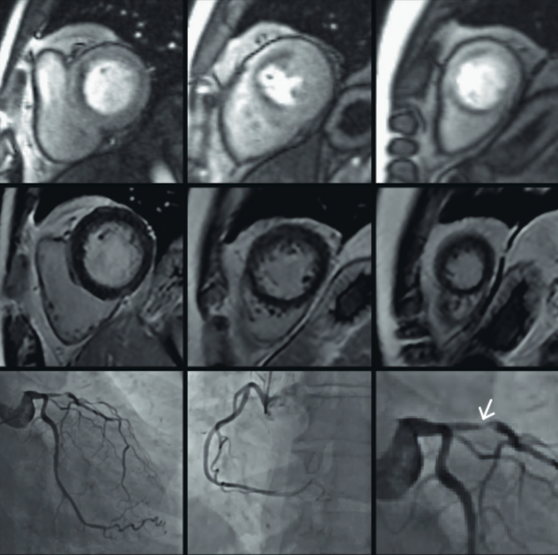

Compressed Sensing heralds the paradigm shift for routine clinical imaging, by providing tremendous acquisition time reductions and gaining new capabilities for 3D imaging, especially in the depiction of dynamic processes or moving organs.

Compressed Sensing offers synergistic enhancement to parallel imaging with sparse sampling and iterative reconstruction, enabling acceleration factors up to 40.